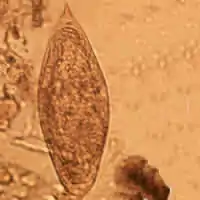

| Egg of Schistosoma intercalatum | |

The clinically defining characteristic of most schistosome species are their eggs' size and shape. The eggs of Schistosoma intercalatum have a terminal spine and tend to be moderately larger than those of S. haematobium (approximately 130 × 75 μm). The origin of the name 'intercalatum' is from the observation that their eggs are of an intermediate range between the smaller S. haematobium and larger S. bovis.[2] These eggs are unique because they will stain red when exposed to the Ziehl–Neelsen technique, aiding in identification.[3] When viewed using scanning electron microscopy, it can be observed that the S. intercalatum's surface has a much lower amount of integumental elevations, or bosses, than S. mansoni. This feature is consistent with the tegument appearance of other terminally spined schistosomes.[4]

Diagnosis is usually made using clinical and epidemiological information. Infection with S. intercalatum can be distinguished from that of S. mansoni or S. haematobium based on where eggs manifest outside the body and the morphology of the eggs. In Africa, the only species of schistosome are S. intercalatum, S. mansoni, and S. haematobium. S. haematobium causes urinary schistosomiasis, so eggs will be shed in the urine; S. mansoni and S. intercalatum reside in the mesenteric venous plexus, so eggs will be shed in the feces.[5] Looking at the stool specimen under a microscope, the species can be distinguished; S. intercalatum eggs have a terminal spine (as seen in the figure above) and S. mansoni eggs have a lateral spine.[12]